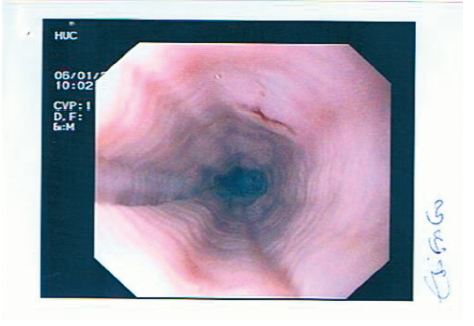

A EDA de controlo, executada 3 semanas após o início do tratamento, identifica esófago com aspeto traqueiforme (fig. 4) e DII com estenose circunferencial em anel, erosionada, mas facilmente franqueável e restos alimentares sólidos a montante. Foram efetuadas biópsias no esófago, estômago e duodeno. O exame histopatológico revelou marcada redução do infiltrado por células eosinofílicas na lâmina própria da mucosa duodenal (menos de 5 eosinófilos por CGA), traduzindo resposta terapêutica (fig. 5). Restantes biopsias sem alterações.

Figura 4 EDA mostrando esófago de aspeto traqueiforme.